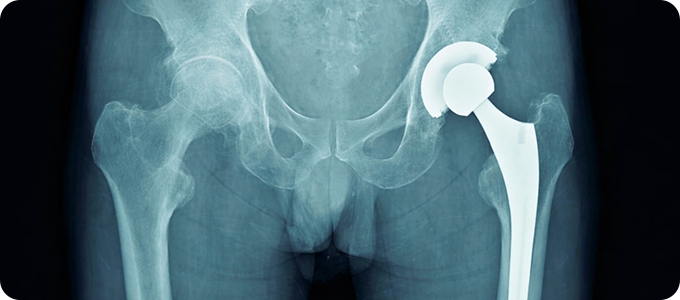

고관절골절

• 허벅지 뼈와 골반의 연결 부분인 고관절에 금이 가거나 부러지는 것입니다.

골절이 발생하면 환자의 움직임이 제한되어 대부분의 시간을 누워 있게 되므로

욕창, 폐렴, 뇌졸중, 심근 경색, 인지 능력 저하 등의 합병증이 나타날 수 있습니다.

• 대부분 넘어지면서 고관절부의 외측을 직접 부딪히면서 발생합니다.

젊은 연령에서는 추락이나 교통사고 같은 고에너지 외상에 의한 것이 대부분입니다.

노인들은 골다공증으로 인해 가벼운 낙상에 의해서도 뼈가 부러질 수 있습니다.

• 골절 후 즉시 허벅지 바깥쪽과 사타구니에 심한 통증이 있습니다.

다리를 움직일 수 없습니다. 고관절을 움직일 경우 더욱 심한 통증이 나타납니다.

골절된 쪽의 다리가 반대쪽에 비해 짧아지며, 발과 무릎이 바깥쪽으로 돌아가있습니다.